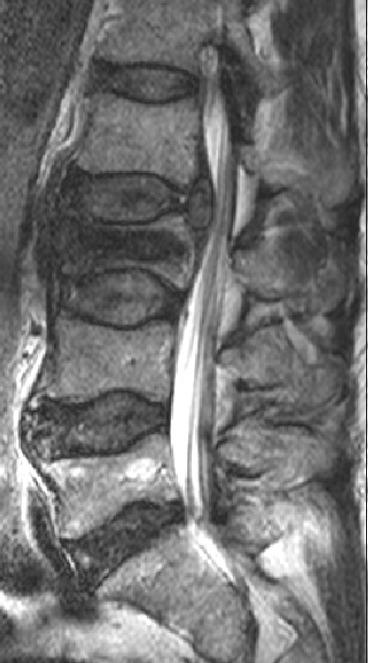

Imaging in cauda equina syndrome--a pictorial review.

Ulster Med J. 2013 May;82(2):100-8.